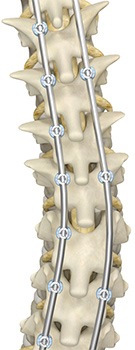

When reaching this step in the operating room, your surgeon positions the Mako Robotic-Arm over the surgical site. Mako Spine is designed to align to your personalized surgical plan. Once aligned, Mako Spine holds a guide tube in place, allowing your surgeon to “prepare the bone” or use instruments to make holes through the bones that connect the back of the vertebrae to the vertebral bodies in the front of the spine. These connecting bones are called pedicles, and the specialized implantable screws placed into them are called pedicle screws. Once the bone is prepared, Mako Spine helps your surgeon place the pedicle screws as planned.

Spine surgery generally involves several steps that may include accessing the affected area of the spine, removing diseased or damaged bone and/or disc material, placing implants, and securing the spinal bones with specialized implantable screws – a process referred to as fixation. Fixation refers to the surgical stabilization of the vertebrae (spinal bones) using specialized implants called screws and rods.